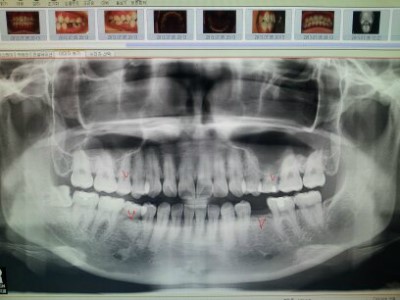

지난번에 찍엇던 3D 촬영사진이에요

요 세 컷을 합체하면 요리조리 위아래 좌우로 돌려가며 볼수잇어서 실물과 많이 흡사해요

빨간색으로 표시해주신 부분을 발치할꺼구요

보통은 치아교정을 할때 송곳니 바로 뒤에잇는 작은어금니를 발치하는데

전 영구치대신 유치인 어금니들이 잇어서 얘들을 발치하게 되요

것도 다행인것이 신기하게 얘들이 다 같은위치에 잇다는;;